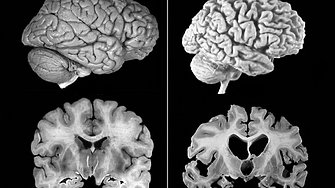

При болестта на Алцхаймер се наблюдава постепенно необичайно натрупване в мозъка на два ключови протеина - тау и бета-амилоид. Това води до смърт на мозъчни клетки, свиване на мозъка, загуба на памет и нарастваща неспособност за изпълнение на ежедневните задачи. Заболяването е един от основните проблеми на общественото здравеопазване, засягащ повече от 40 милиона души по света.